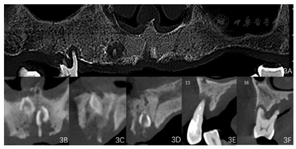

影像学检查:曲面体层片及根尖片示13、16、42、38、48牙槽骨吸收至根尖;剩余牙牙槽骨吸收至根长1/2。CBCT示上颌正中多生牙,多生牙舌侧可见不规则低密度影像。(图2、图3)

术前CBCT检查上颌骨量显示,12 mm>前牙区骨高度≥8 mm,骨宽度<6 mm;12 mm>右侧后牙区骨高度≥8 mm;左侧后牙区骨高度<4 mm,骨宽度<6 mm。依据Carames[9]全牙列综合种植解决方案分类,属于复杂种植方案设计,如全牙列行种植后固定义齿修复,需设计6颗种植体。种植体设计有4种方案,其中3种方案涉及到2颗斜形种植体在上颌窦前侧壁的种植及后牙区的穿颧或穿翼种植;另一种种植方案是双侧后牙区骨增量,左右各种植3颗种植体,本病例6颗种植体的设计方案与上述解决方案一致,所不同的是在导板定位的情况下利用了前牙区、前磨牙区及右侧后牙区的有效骨量轴向种植5颗种植体,因左侧后牙区颊侧骨壁吸收多,该区骨宽度及高度均不足,因此在种植同期对左侧后牙区实施了上颌窦侧壁开窗提升植骨技术,术后6个月在左侧后牙区轴向植入1颗种植体,规避了双侧上颌窦前侧壁区斜形种植及双侧后牙区穿颧及穿翼种植,降低了手术难度及风险,患者接受度高。